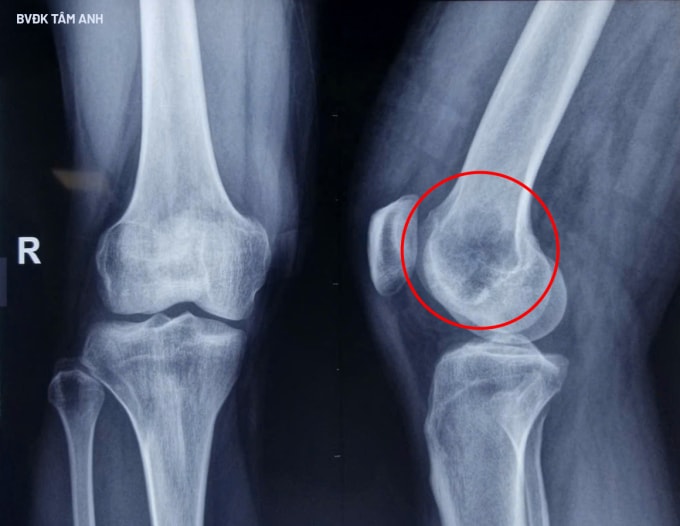

Anh Tài có tiền sử mắc bệnh gout và thoát vị đĩa đệm, điều trị nội khoa thời gian dài. Gần đây anh đau âm ỉ vùng cột sống lưng, đau tăng khi đi lại, lan xuống mông, chuyển nặng nhanh. Các bác sĩ nghi ngờ có bệnh lý tiềm ẩn phối hợp, chỉ định anh Tài tầm soát xét nghiệm đo nồng độ FGF23 trong huyết thanh tăng cao kết hợp chụp PET/CT khảo sát toàn thân. Kết quả xác định người bệnh có khối u ẩn ở vùng lồi cầu xương đùi phải, kích thước 32x25x42 mm, sau sinh thiết xác định là u trung mô phosphaturic.

Các bác sĩ chỉ định phẫu thuật nạo lấy khối u lồi cầu trong xương đùi phải kết hợp mài cao tốc tăng cường giúp giảm nguy cơ tái phát u. Sau đó, êkíp đổ xi măng sinh học lấp khuyết hổng lớn mà khối u để lại và tái tạo vùng lồi cầu đùi bằng vách vỏ xương mào chậu cùng bên. Phương pháp này giúp giữ lại nguyên vẹn chi thể và hình dạng khớp gối bình thường cho người bệnh, bảo tồn chức năng vận động chi thể.